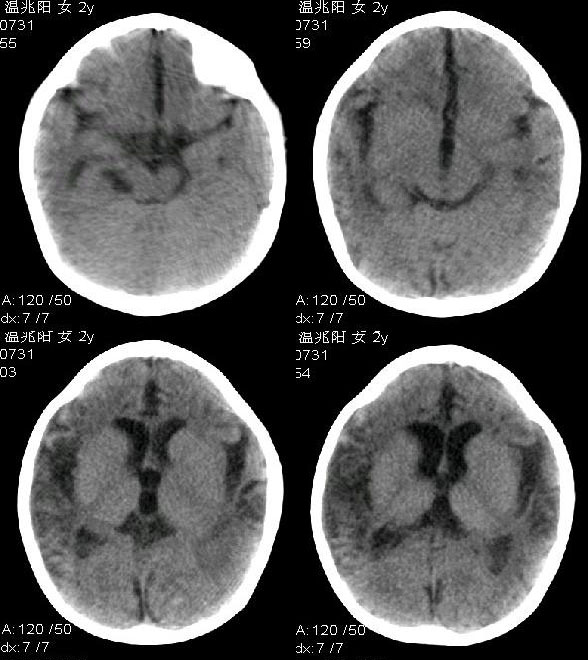

2岁智低体弱女婴脑部ct平扫示

额、颞、顶叶

皮质变薄(脑沟裂增宽)伴灶性梗死(小灶脑脊液样低密度影)、

白质减少(脑室增大)并变性(脱髓鞘所致的较对称分布的灶性近似脑脊液密度的低密度灶,个别与脑室穿通)、

颞枕叶交界脑质近凸面点索样钙化灶

考虑多为

化脑后遗改变(脑萎缩、灶性脑软化形成)

——婴幼儿脑组织尚处于继续发育阶段,单纯说脑萎缩不确切,我觉得说脑萎缩伴发育不良更好些。

这种脑萎缩及脑软化灶形成不可逆转,所以此婴预后不良。